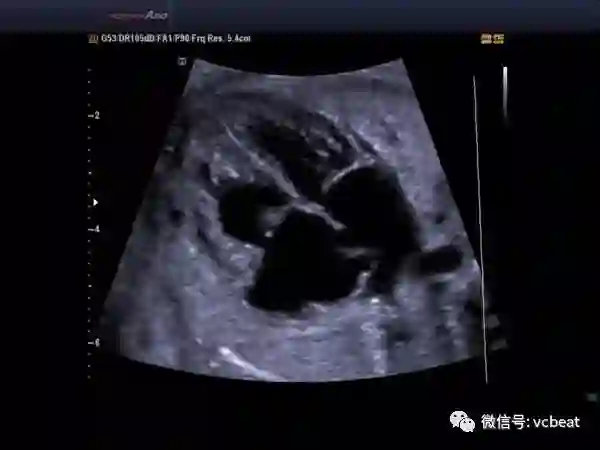

医学超声波检查作为一种常规的检查手段,已经广泛的应用在临床。它的工作原理与声纳有一定的相似性,即将超声波发射到人体内,当它在体内遇到界面时会发生反射及折射,并且在人体组织中可能被吸收而衰减。

因为人体各种组织的形态与结构是不相同的,因此其反射与折射以及吸收超声波的程度也就不同,医生们正是通过仪器所反映出的波型、曲线,或影象的特征来辨别它们。

超声诊断仪在临床上应用最广的是B型超声和D型超声,即人们通常所说的B超和多普勒超声。由于超声具有无创、高灵敏度、应用面广、低成本和操作方便等优点,被广泛应用于临床诊断,尤其是胸部脏器、心脏、眼科和妇产科的诊断。